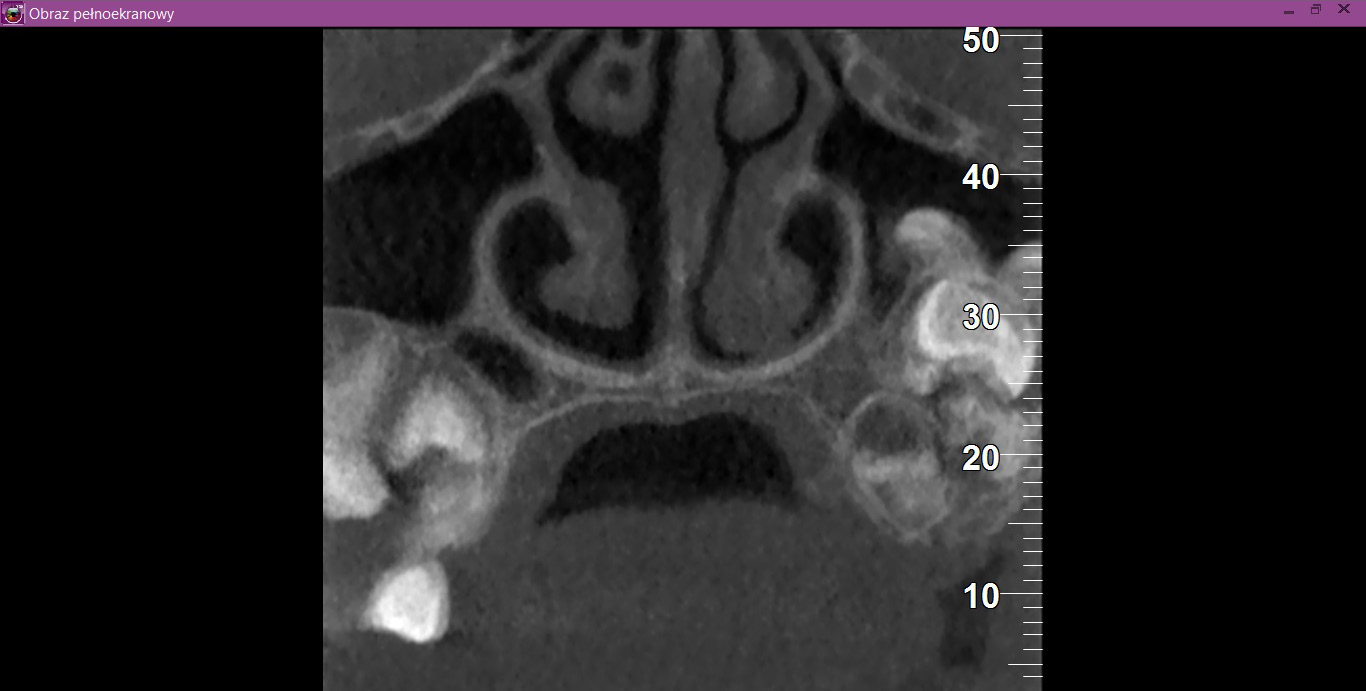

Recently, there has been improvement in X-ray diagnostic imaging methods, especially with regard to CBCT, which certainly facilitates arriving at diagnosis as early as at the stage of radiological examination. Jayam et al. describe a case of an 11-year-old girl with a radiological picture (panoramic radiography, a tooth X-ray and a maxillary occlusal radiograph) description of impacted tooth 11 with an additional cusp and an extensive dentigerous cyst.2 In the course of marsupialization, the dentigerous cyst was found to have no contact with tooth 11, while it contacted the adjacent additional cusp. On histopathological examination, OCp was diagnosed with a cyst. According to some authors, X-ray images – panoramic radiographs and targeted dental X-rays – may not accurately reveal the pattern of the lesion, which is why cross-sectional CBCT is recommended in the case of doubts or for more accurately determining the location.2 In the case of 2 of our patients, it was not until a CBCT was performed that the adequate diagnosis was reached, and it was later confirmed during the procedure and histopathological examination. The first patient was a 9-year-old girl referred to an orthodontist in our clinic due to impacted tooth 21 for the exposure of the tooth and the application of a bracket to the crown of tooth 21. The patient had with her a current panoramic radiograph with visible impacted tooth 21, showing a small non-distinctive radiopacity in the tooth crown, which could be consistent with an additional cusp. An X-ray of tooth 21 was performed at our clinic, revealing a non-distinctive area of radiopacity next to the crown of tooth 21 (Figure 7). The patient was referred for cross-sectional CBCT. After verification, OCp was diagnosed and removed with its capsule, and an orthodontic bracket was attached to tooth 21 in local anesthesia (Figure 8). Histopathological examination confirmed the preliminary diagnosis of OCp. The other patient was a 5-year-old girl who was admitted to our clinic with a missing deciduous tooth 65. The patient had a current panoramic radiograph with her, revealing an impacted tooth (most probably tooth 65) with a non-distinctive area of radiopacity (Figure 9). Cross-sectional CBCT was recommended. In the X-ray image, the preliminary diagnosis suggested OCp with the impacted deciduous tooth 65 above it and the tooth bud of permanent tooth 25 on the palatal side (Figure 10). The procedure involved the resection of the impacted deciduous tooth 65 and the enucleation of the odontoma with its capsule; the tooth bud of tooth 25 was left. Due to the child’s age and her poor cooperation, the procedure was carried out in general anesthesia. Histopathological findings revealed OCp.